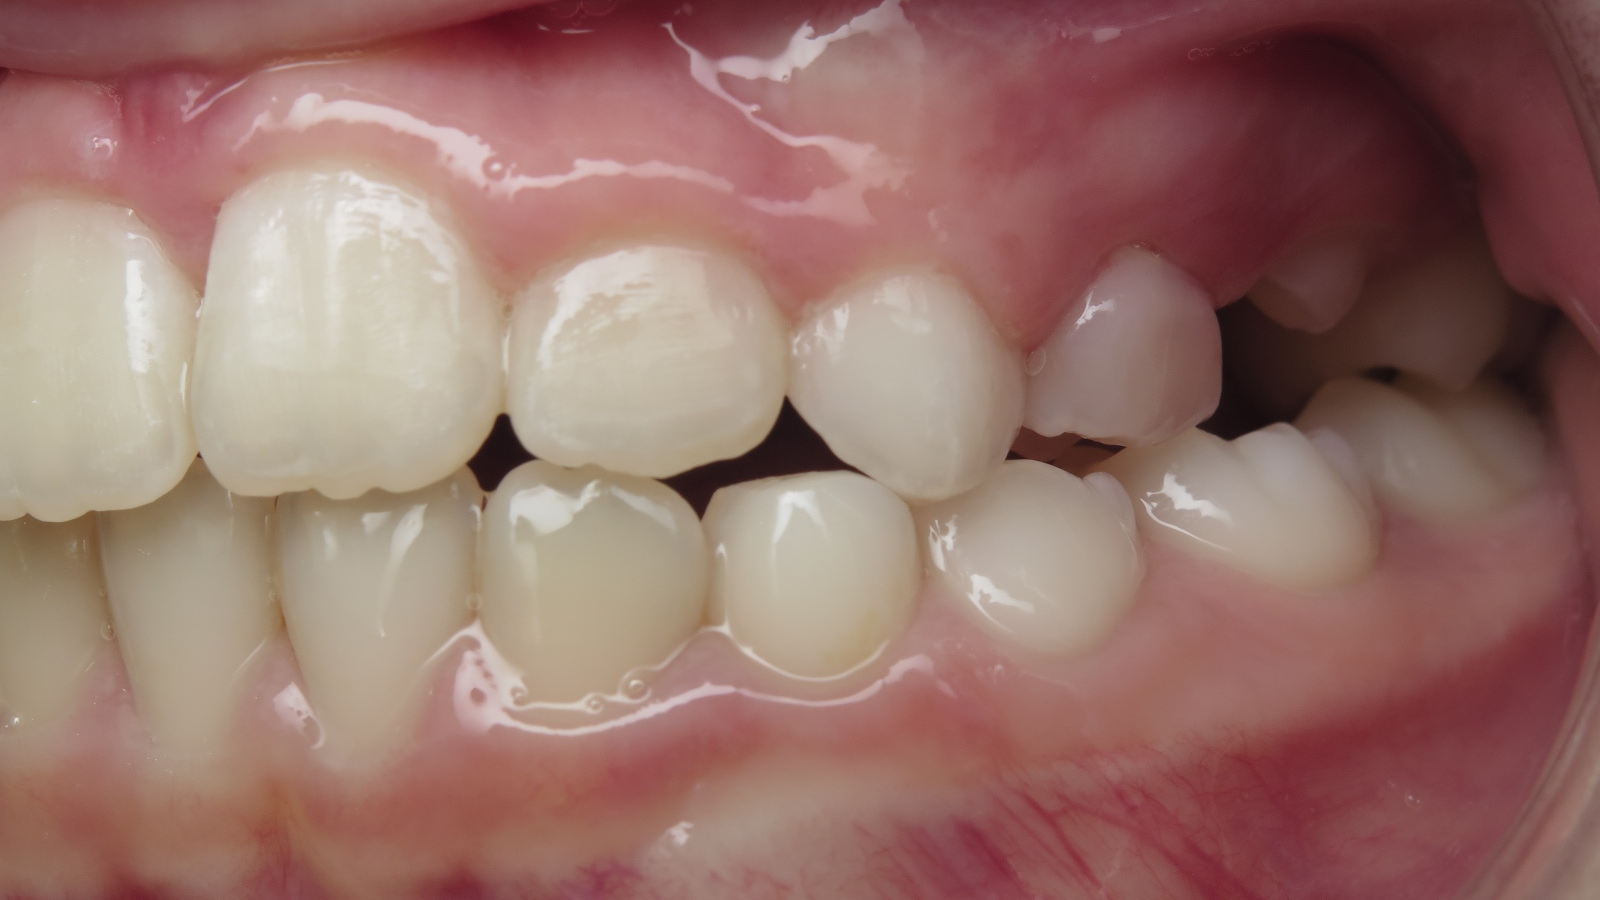

appareillage sectionnel multibagues pendant 18 mois

surveillance évolution de la dentition en cours

bilan début et en cours de traitement